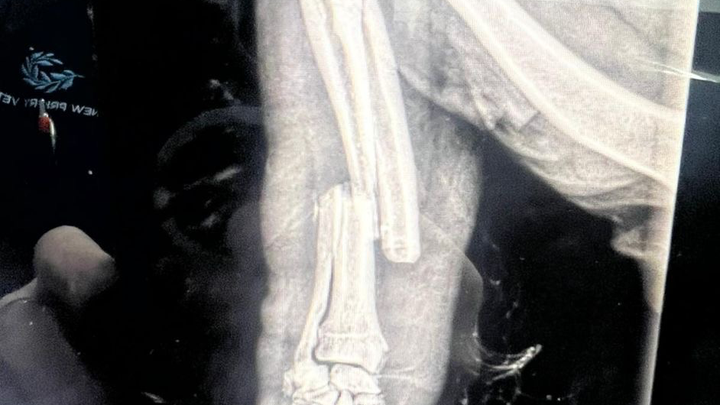

Hi my name is Coral and I’m an eighty year old living with my lovely Cavapoo called Rara. On Friday afternoon she was attacked by two Stafford/Bullie type on a bus in Brighton. She is being cared for at a very caring vets in Brighton but the bill is escalating due to the fact that she is on intravenous medication for pain relief, antibiotics and fluids waiting for an operation to pin and plate her lower front leg that has breaks in her Tibia and Fibula. The operation is scheduled on Wednesday and if there is no infection in the bone from the bit they are hoping to save her leg from amputation. I had pet insurance but the maximum for treatment is £1000 and this will run into many thousands. Any help would be so appreciated.